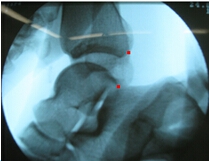

在外踝韧带损伤时,应力位摄片和磁共振(MRI)影像研究进展迅速,这为准确诊断和确定治疗方案创造了条件。应力位的摄片对于可靠地判断韧带是否断裂非常重要,尤其是慢性损伤,需要考虑行断裂韧带重建术时,我们应尽量完成此项检查。通常应力位检查包括:1判断距腓前韧带损伤的前抽屉试验(anterior drawer test),2判断距腓前韧带损伤的距骨倾斜试验(inversion talar tilt test)。前抽屉试验是固定踝关节近端,跖曲20°牵拉踝关节远端向前时,比较胫骨和距骨后缘与力线的距离(图4),距骨前移超过5 mm(与对侧比较)为可疑阳性,超过9 mm为阳性;van Dijk等证实该检查的敏感度73%,特异度97%。距骨倾斜试验是固定踝关节近端,对踝关节远端施以内翻应力,评估胫距关节面夹角(图5);评判标准:与对侧比较,大于5°为可疑阳性,超过10°为阳性;或者单侧超过15°为阳性。踝关节轻微跖曲时应力位查体比轻微背曲时,更容易获得阳性表现。当然非应力位下实施的常规X线片,例如踝关节正侧位、踝穴位、足正侧位等有助于排除踝关节骨折、力线异常、骨赘、局灶性骨坏死等需要鉴别诊断的疾病。踝关节磁共振(MRI)检查,对于判断踝关节韧带损伤具有重要价值,韧带结构在T1和T2相呈低信号,韧带断裂表现为韧带结构连续性中断,或者正常低信号结构消失。为了清楚显示ATFL结构,需要采用斜横断位扫描才能显示ATFL全长,此时舟骨恰呈“哑铃状”(图6)。踝关节三维CT检查,不是踝关节韧带损伤的常规检查,但是对判断外踝小骨块是哪根韧带的撕脱性骨折,还是游离体,或者是腓骨肌腱的籽骨,具有重要的参考价值,这对于完善术前治疗方案有较大帮助。

4A

4B

A:操作手法;B:摄片阳性,红点分别代表胫骨和距骨后缘

图4 左踝前抽屉试验